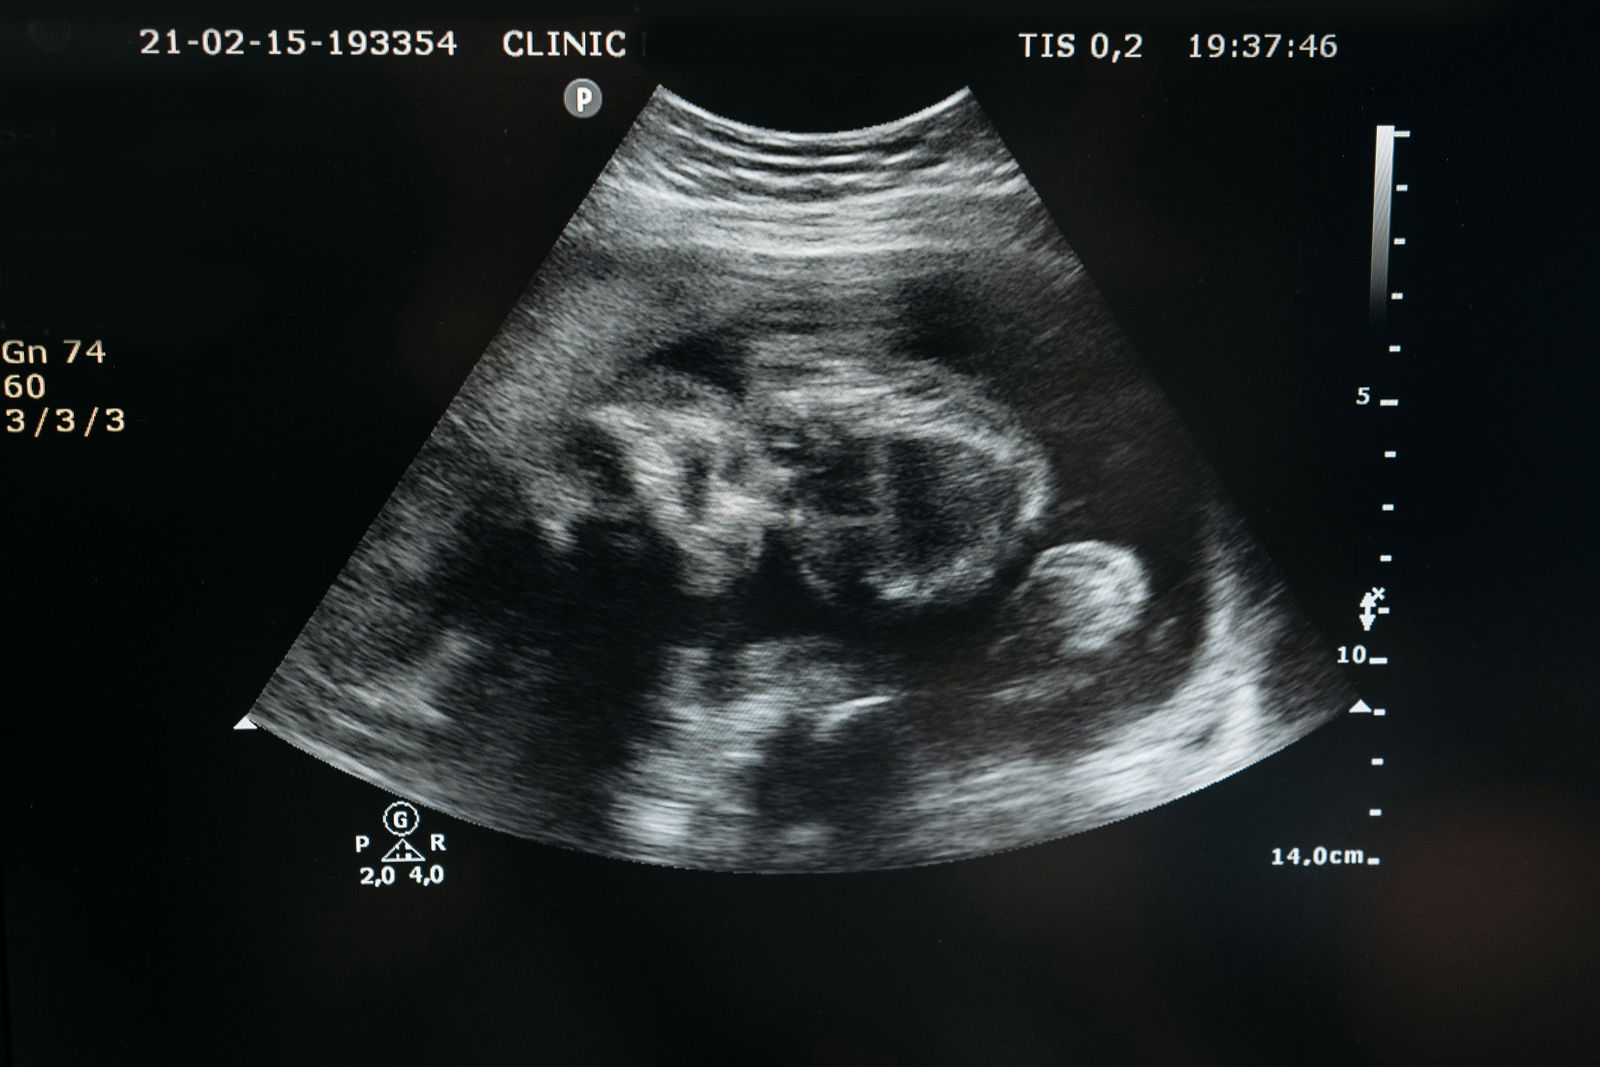

Hugo Powell, geboren in Londen met een gewicht van 3,09 kilogram, is de eerste Britse baby van een moeder met een baarmoeder van een overleden donor, dat meldt The Telegraph Zijn moeder, Grace Bell, een IT-programmamanager, heeft het Mayer-Rokitansky-Küster-Hauser-syndroom (MRKH), een aandoening waardoor ze op natuurlijke wijze geen kinderen kon krijgen.

Na de transplantatie in 2024 begon Bell met een vruchtbaarheidsbehandeling en beviel ze in december vorig jaar met succes van Hugo. Overweldigd door vreugde beschreef ze de ervaring als een “wonder” en sprak ze haar diepe dankbaarheid uit jegens de donor en hun familie voor hun buitengewone vrijgevigheid. Dankzij de baarmoederdonatie kon Bell haar levenslange droom om moeder te worden verwezenlijken.

Hugo’s tweede naam, Richard, is een eerbetoon aan prof. Richard Smith, een sleutelfiguur in het baarmoedertransplantatieprogramma van het Imperial College Healthcare NHS Trust. Smith, die aanwezig was bij de geboorte van Hugo, beschreef de zwangerschap als “ongelooflijk” en prees de teamprestatie die deze baanbrekende prestatie mogelijk heeft gemaakt.

Wereldwijd zijn er ongeveer 25-30 baby’s geboren dankzij een baarmoederdonatie van een overleden donor. Hoewel de meeste baarmoedertransplantaties plaatsvinden met levende donoren, komen donaties van overleden donoren steeds vaker voor. (fc)